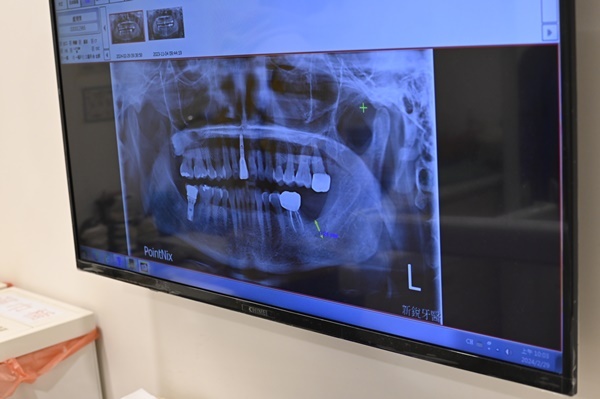

劉醫師在術前花了很多時間為我進行詳細的口腔評估,透過如圖所示的數位X光影像分析,清楚讓我了解自己的骨質狀況、缺牙位置與神經分佈,整個流程超專業卻也親切,完全打破了我對傳統植牙「看不懂就只能相信醫師說法」的印象。